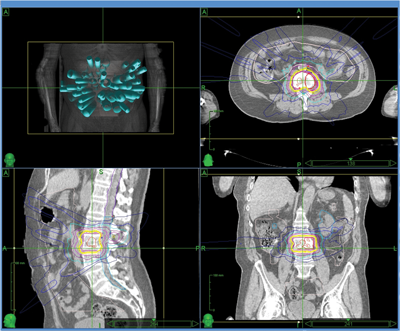

Figure 2 (top and above): Isolated metastasis at L3 vertebral body.

A 61-year-old man initially treated in January 2001 for an organ confined Gleason 3+4 prostate cancer with radical prostatectomy. His initial postoperative prostate specific antigen (PSA) was undetectable but rose to 0.3 in 2005 for which he received prostate bed salvage radiotherapy, after which his PSA again dropped to an undetectable level. Subsequently however, his PSA rose to 12 in 2010 at which point he was started on androgen suppression leading to a relatively short period of biochemical control. At the time of biochemical progression on androgen suppression (castrate resistant disease) the only site of disease which could be demonstrated was an asymptomatic L3 vertebral metastasis (Figure 2). Following careful discussion the patient opted to receive stereotactic radiotherapy (see radiotherapy plan - Figure 3) receiving 24Gy in three fractions over three consecutive days. He reported no toxicity from his radiotherapy.

Figure 3: Stereotactic radiotherapy plan to isolated L3 metastasis.